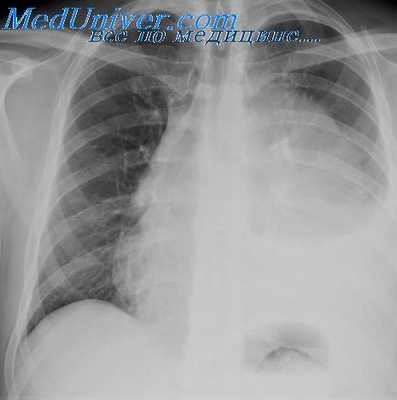

Рентгенологическое исследование: справа в верхнем отделе переднего средостения определяется овальной формы однородное интенсивное затемнение размером около 4 X 9 см с правильно выпуклым четким контуром). Это затемнение непосредственно прилегает к неизмененной трахее и в боковой проекции теряет свои четкие очертания. При глотании оно смещается вверх.

На рентгенокимограммах по контуру тени видны малой амплитуды зубцы сосудистого типа. Со стороны легких и их корней патологических изменений не определяется. Куполы диафрагмы подвижны, синусы свободны.

Со стороны сердца явления дистрофии миокарда. Аорта не изменена. Учитывая локализацию тени в верхнем отделе переднего средостения, а главное ее смещение вверх при глотании, решили, что у больного имеется внутригрудной зоб.

На операции (Е. С. Лушников) выявлена дермоидная киста, дугообразно охватывающая трахею спереди и с боков и плотно с ней спаянная. Киста полностью удалена, и больной на 24-й день выписан в удовлетворительном состоянии.